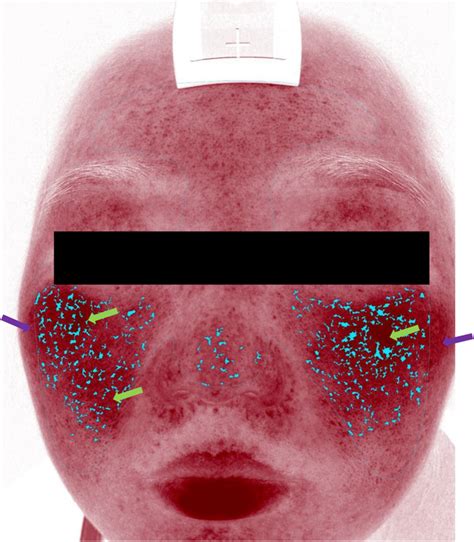

Now that you’ve got ImageJ NIH up and running, let’s talk about what makes this software a powerhouse. ImageJ NIH isn’t just a pretty face; it’s packed with a staggering array of features that cater to virtually any image analysis task you can throw at it. One of its most fundamental strengths is its measurement capability . You can easily measure distances, perimeters, areas, and even calculate the angle between lines. This is crucial for quantitative analysis, allowing you to get precise numerical data from your images. Need to know the size of a cell, the diameter of a blood vessel, or the area covered by a lesion? ImageJ makes it simple. It even supports calibrations , so you can relate pixel dimensions to real-world units (like micrometers or millimeters), ensuring your measurements are scientifically meaningful. Beyond simple measurements, ImageJ excels at intensity analysis . You can generate histograms to understand the distribution of pixel values, identify thresholding levels to segment specific regions of interest, and quantify the average intensity within selected areas. This is invaluable for applications like fluorescence microscopy, where you might want to quantify protein expression or track changes in cellular signals. For those working with 3D data, like stacks of confocal microscope images, ImageJ offers robust 3D visualization and analysis tools . You can create 3D reconstructions, view your data from different angles, and even perform measurements in three dimensions. It’s like having a virtual 3D model of your sample right on your screen! Furthermore, ImageJ supports a vast range of image processing operations . This includes basic adjustments like brightness, contrast, and color manipulation, as well as more advanced techniques like filtering (e.g., Gaussian blur, median filter), edge detection, and morphological operations. These tools are essential for enhancing image quality, highlighting features of interest, and preparing images for further analysis. And let’s not forget about macros and scripting ! ImageJ allows you to record your actions as macros, which can then be replayed to automate repetitive tasks. For more complex workflows, you can write scripts in languages like JavaScript or Python, giving you incredible flexibility and power to customize your analysis pipeline. This automation is a huge time-saver, especially when dealing with hundreds or thousands of images. The sheer breadth of core functionalities makes ImageJ NIH an indispensable tool for any researcher serious about extracting meaningful information from their images.